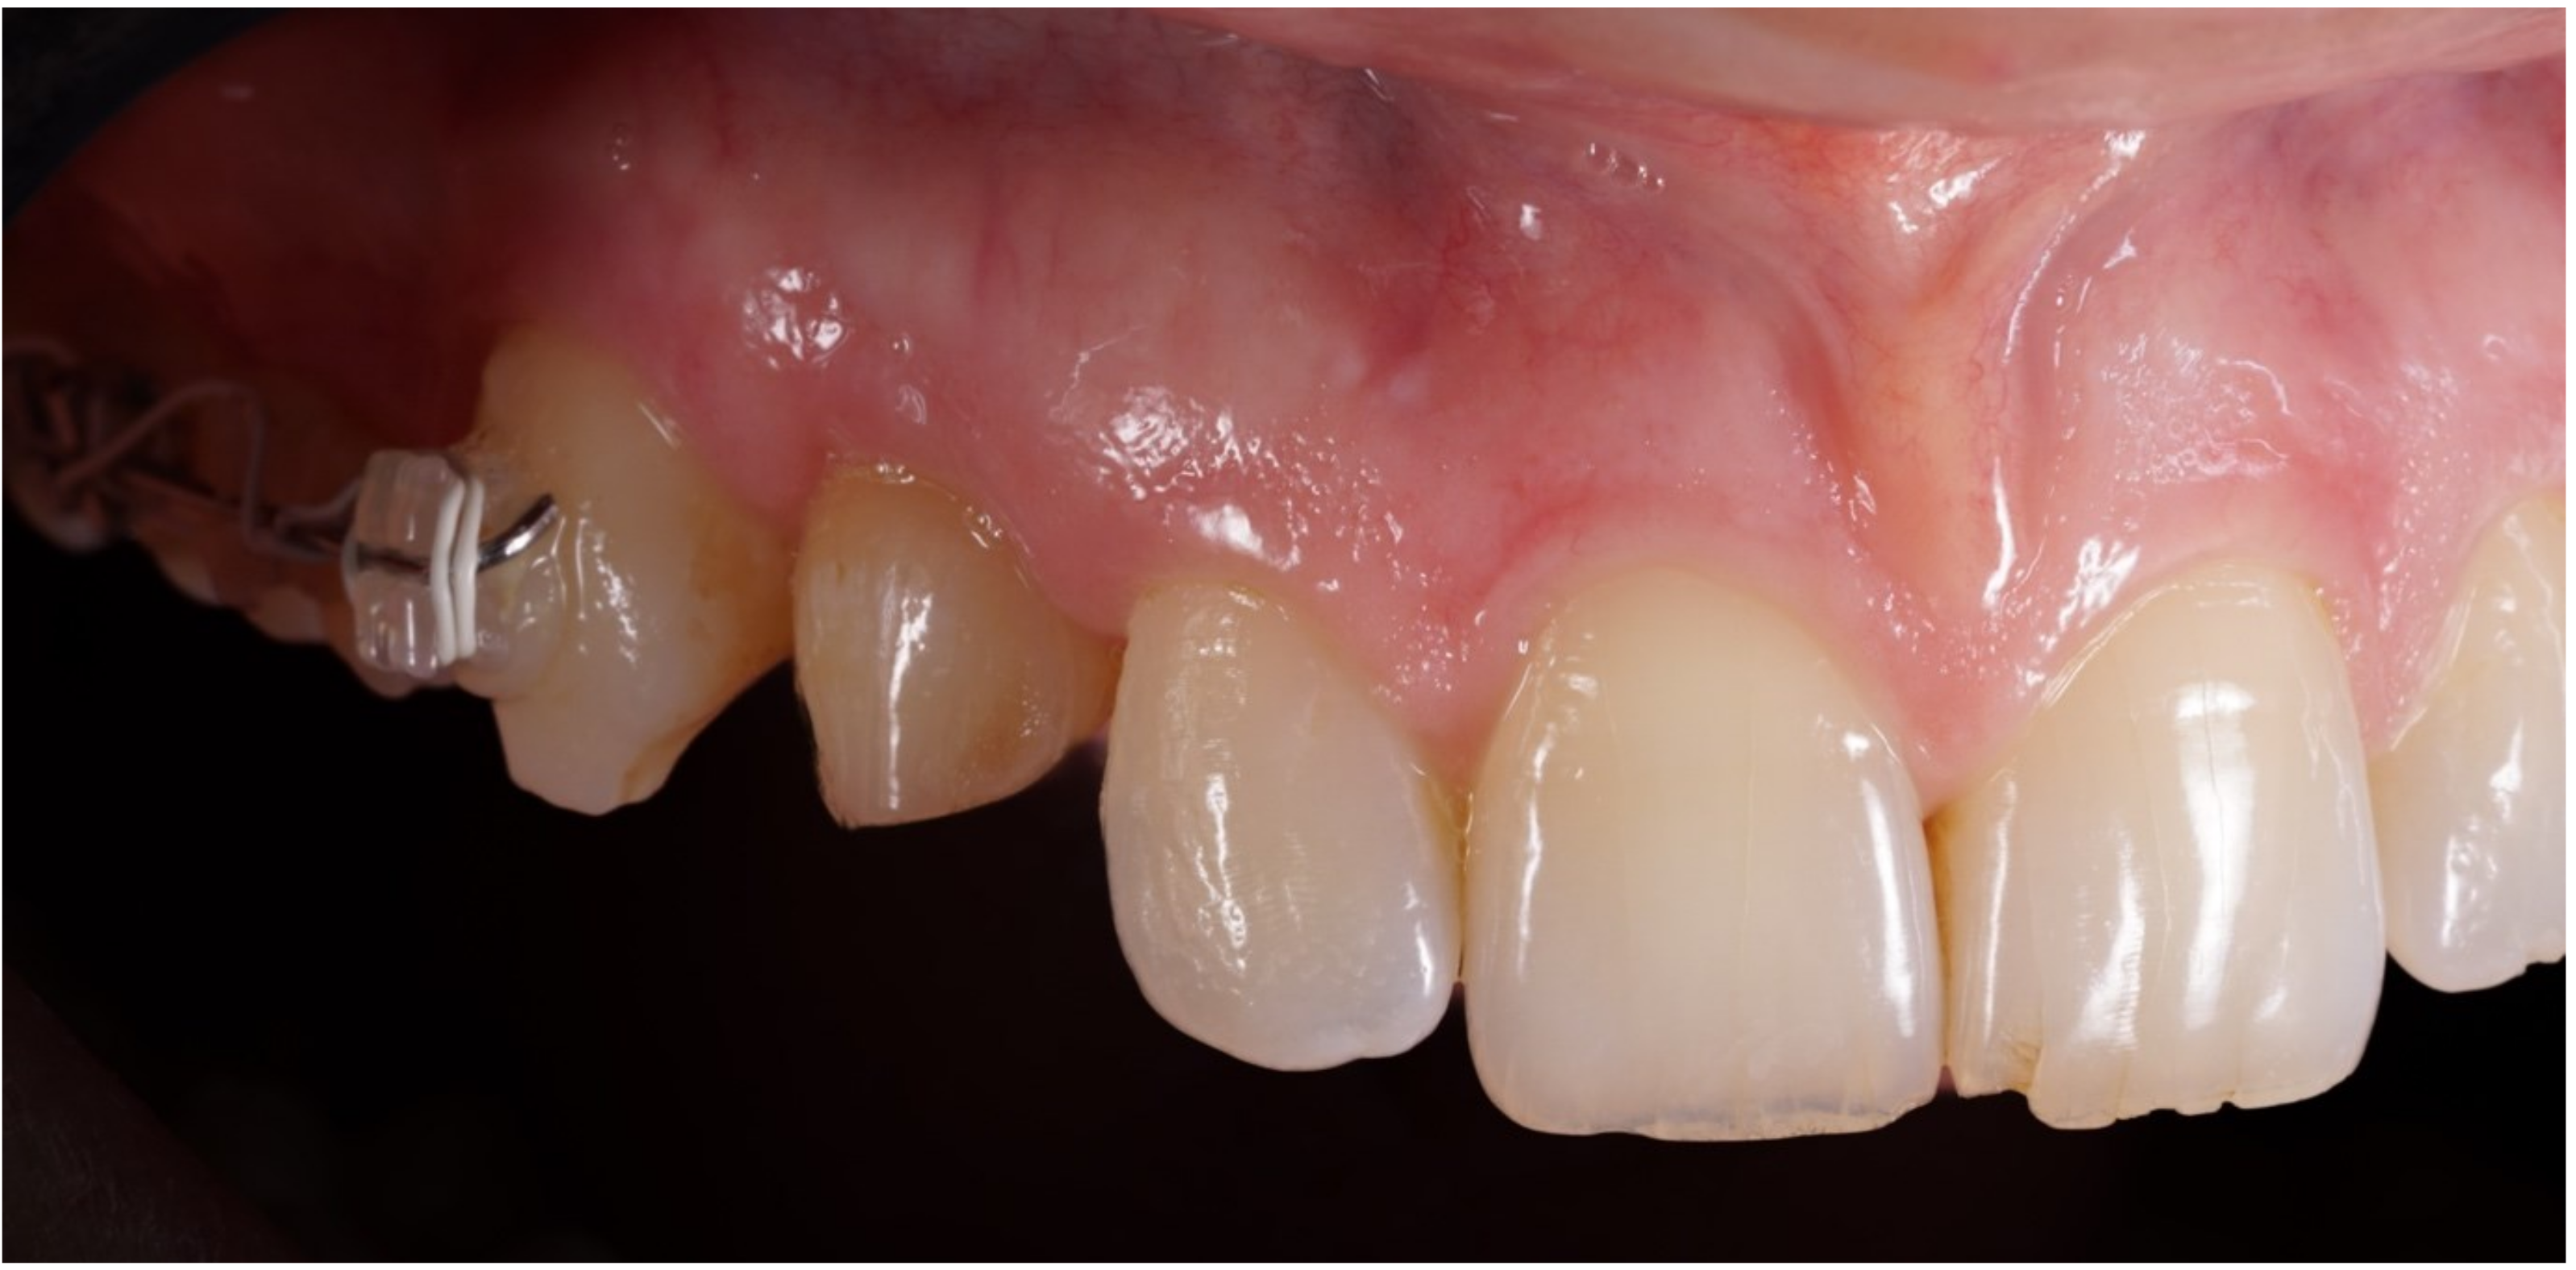

Figure 6.

Healing of soft tissues around the temporary crown.

Figure 7.

Scan abutment in position to record intraoral scan.